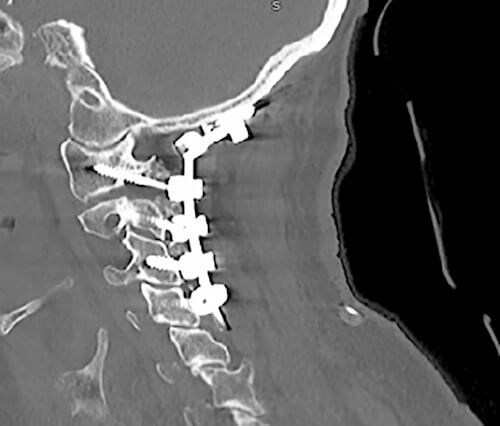

Nach acht Tagen kann er entlassen werden, jedoch kehrt er nach zwei Monaten mit einer Anämie zurück. Die Medikamente hatten zu gastrointestinalen Blutungen aus Zwölffingerdarmgeschwüren und einer Nephropathie geführt. Die Ärzte führen eine Mikroembolisation durch und ändern die Medikation. Von nun an geht es dem Patienten besser, sodass zeitnah auch eine C1-C2-Laminektomie und Dekompression des Rückenmarks mit okzipitaler Fusion durchgeführt werden kann.